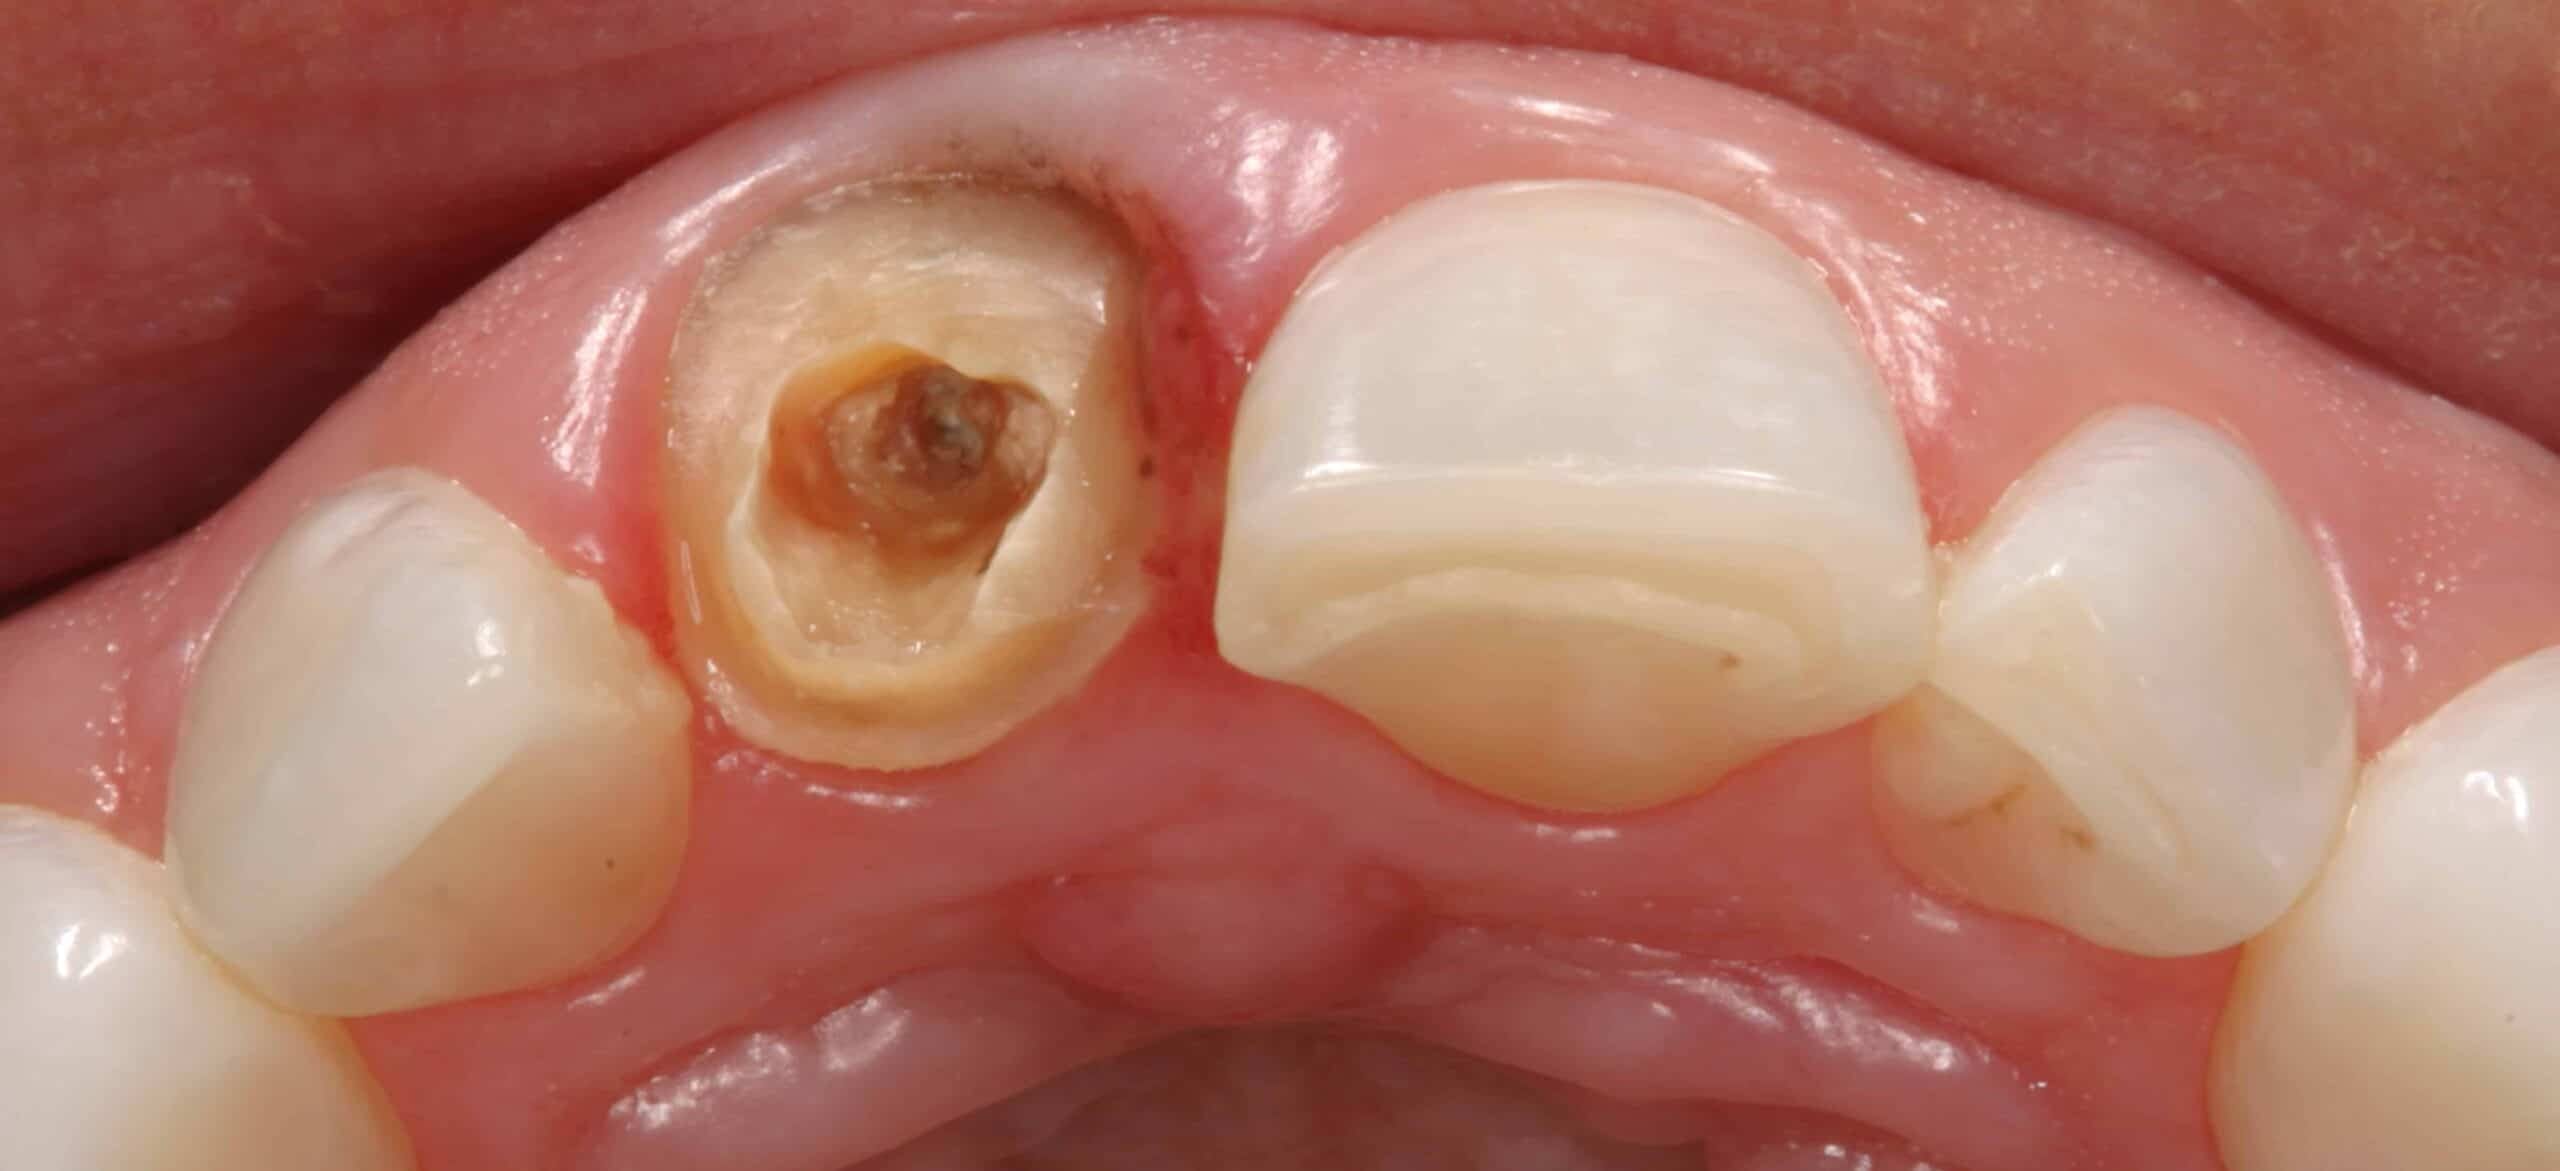

Before:Â Fractured/failed heavily treated upper right central incisor (tooth #8). The root is non-restorable and requires removal. The treatment of choice is a single implant supported restoration.